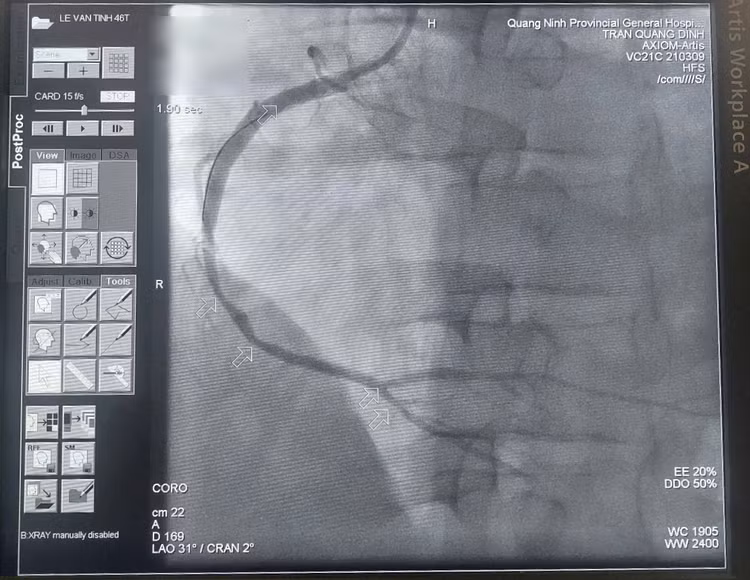

Sau nỗ lực cấp cứu căng thẳng, tri giác người bệnh hồi phục, có huyết áp, điện tim phục hồi nhịp xoang. Kíp can thiệp Bệnh viện Đa khoa tỉnh tiếp tục thực hiện đặt stent để tái thông lòng mạch bị hẹp tắc, khôi phục tưới máu cho cơ tim.

Chúng tôi đã nỗ lực sốc điện cấp cứu 15 lần để cứu người bệnh bằng mọi giá. May mắn là những quyết tâm của chúng tôi được đền đáp, trái tim bệnh nhân đã đập trở lại, huyết áp dần ổn định. Kíp can thiệp sau đó tiếp tục đặt stent để tái thông mạch vành phải bị tắc hoàn toàn.

| Kíp bác sĩ khoa Phẫu thuật và Can thiệp Tim mạch đặt stent tái thông mạch vành phải - Ảnh BSCC |